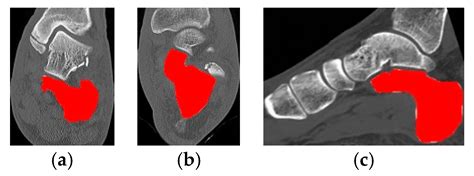

Real-Time Automated Segmentation and Classification of Calcaneal ...